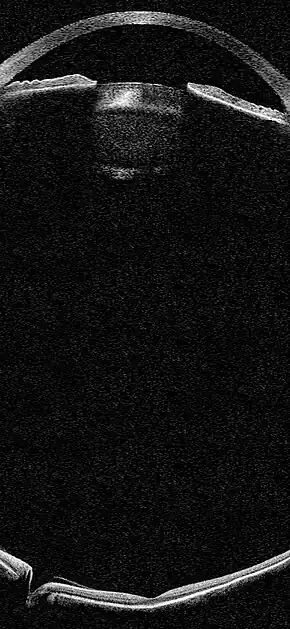

Simulation of an OCT biomicroscopic image of the eye

OCT Biomicroscopy is the use of optical coherence tomography (OCT) in place of slit lamp biomicroscopy to examine the transparent axial tissues of the eye.[1] Traditionally, ophthalmic biomicroscopy has been completed with a slit lamp biomicroscope that uses slit beam illumination and an optical microscope to enable stereoscopic, magnified, cross-sectional views of transparent tissues in the eye, with or without the aid of an additional lens.[2] Like slit lamp biomicroscopy, OCT does not penetrate opaque tissues well but enables detailed, cross-sectional views of transparent tissues, often with greater detail than is possible with a slit lamp. Ultrasound biomicroscopy (UBM) is much better at imaging through opaque tissues since it uses high energy sound waves. Because of its limited depth of penetration, UBM's main use within ophthalmology has been to visualize anterior structures such as the angle and ciliary body. Both ultrasound and OCT biomicroscopy produce an objective image of ocular tissues from which measurements can be made. Unlike UBM, OCT biomicroscopy can image tissues with high axial resolution as far posteriorly as the choroid (Figure 1).